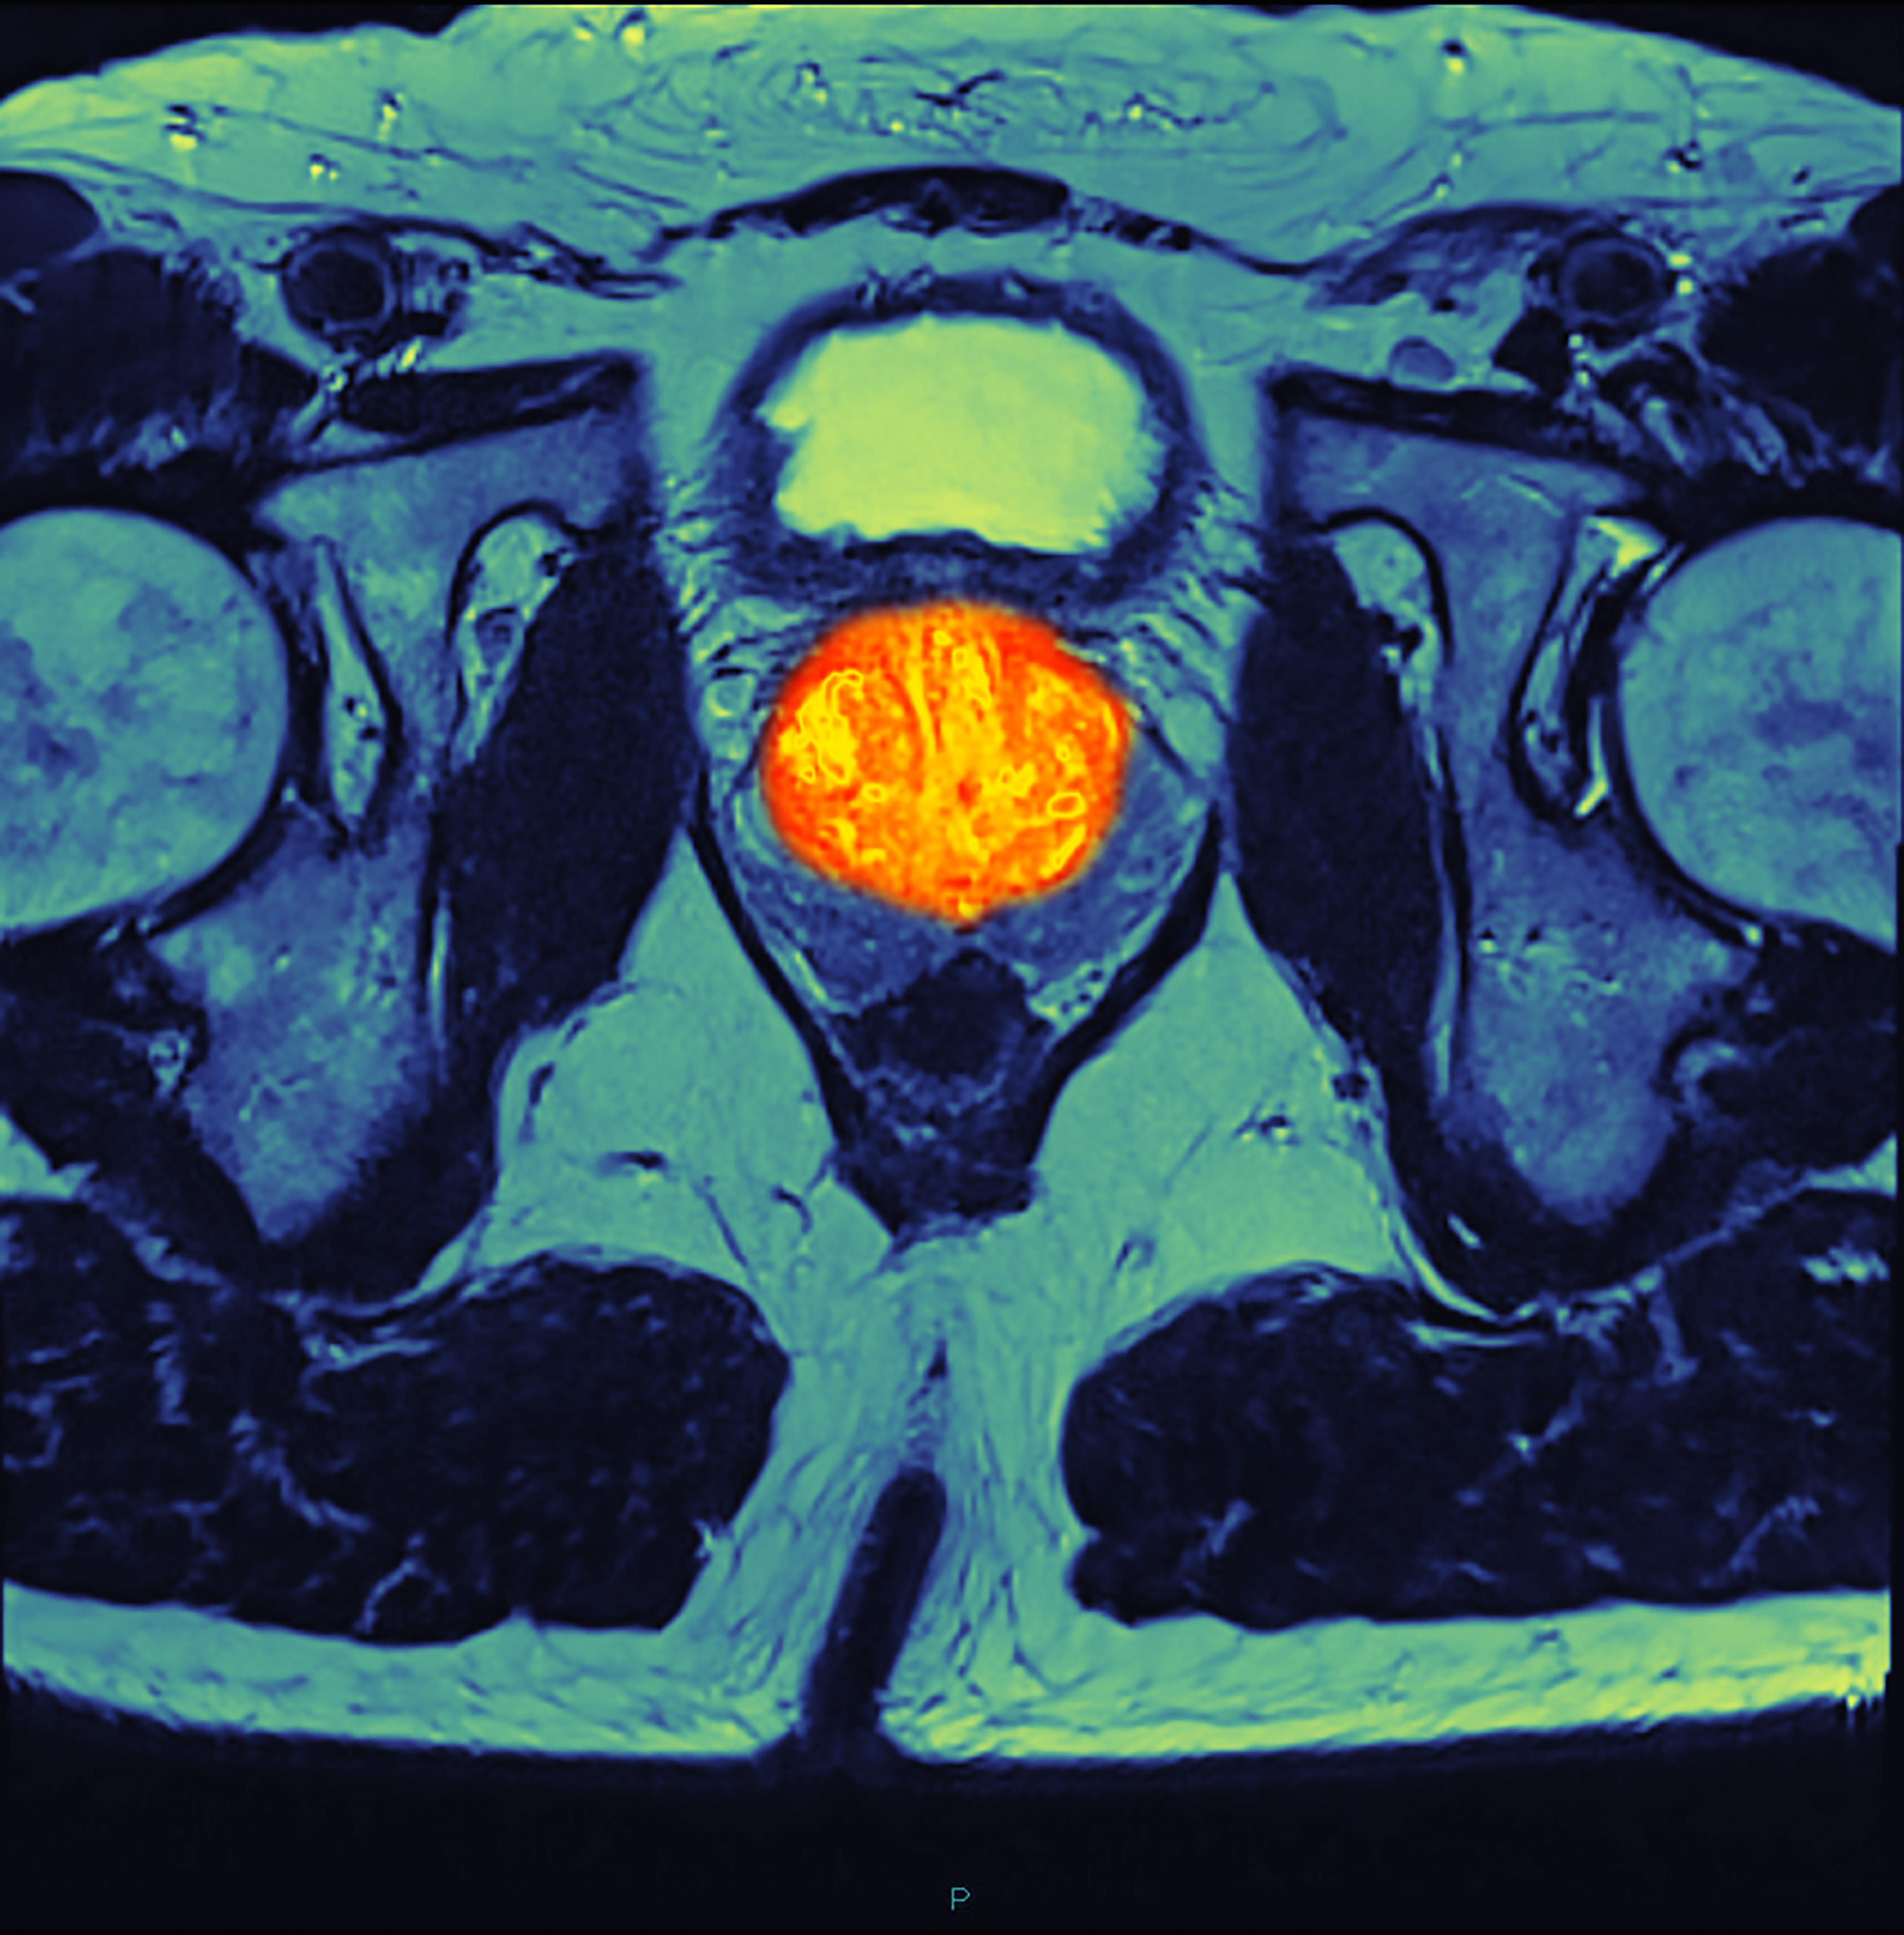

The first session will focus on physicians' perspectives on the use of imaging in patient care for various cancers, including glioblastoma, breast cancer, prostate cancer, and HCC/kidney cancer. The second session will delve into advanced MRI techniques for cancer, such as diffusion-weighted imaging (DWI), dynamic contrast-enhanced (DCE) MRI, magnetic resonance spectroscopy (MRS), and chemical exchange saturation transfer (CEST). The third and fourth sessions will explore the applications of cancer imaging, including genotyping and phenotyping, early detection, stratification, risk characterization, biomarkers for predicting and monitoring therapy response, and image-guided and adaptive therapy. Specific imaging techniques and applications, such as prostate bi-parametric screening, preclinical imaging, PET/MR, radio-genomics, MR-Linac, and intra-operative MRI, will be discussed.